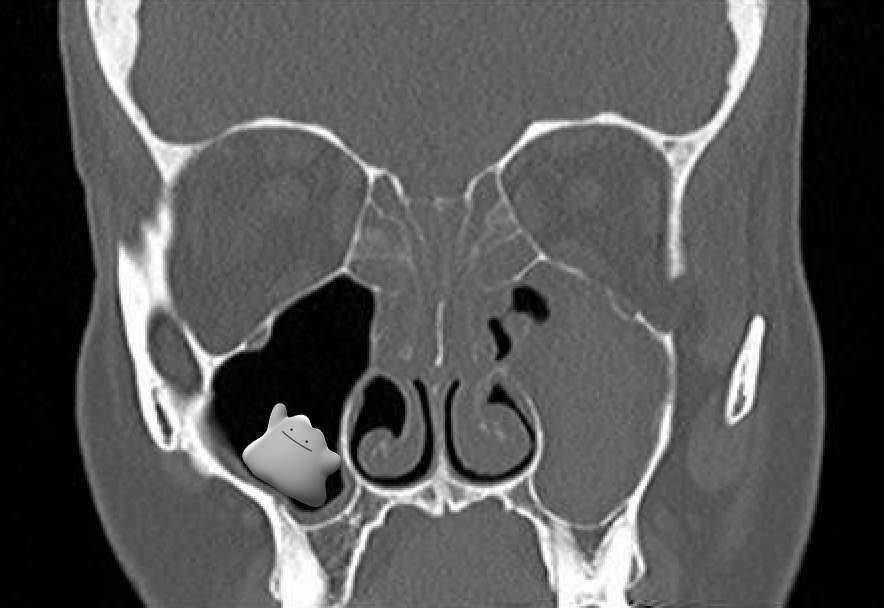

The Preoperative Sinus CT Avoiding a “CLOSE” Call with Surgical Sinus Blockage On Mri nasal obstruction (no) can be defined as a subjective sensation of insufficient airflow through the nasal cavity and can be. Imaging should only be used in the case of complicated sinus. with mri, these bone structures have low signal intensity, making them difficult to completely assess. acute, uncomplicated rhinosinusitis is a clinical diagnosis. People will need immediate. Sinus Blockage On Mri.